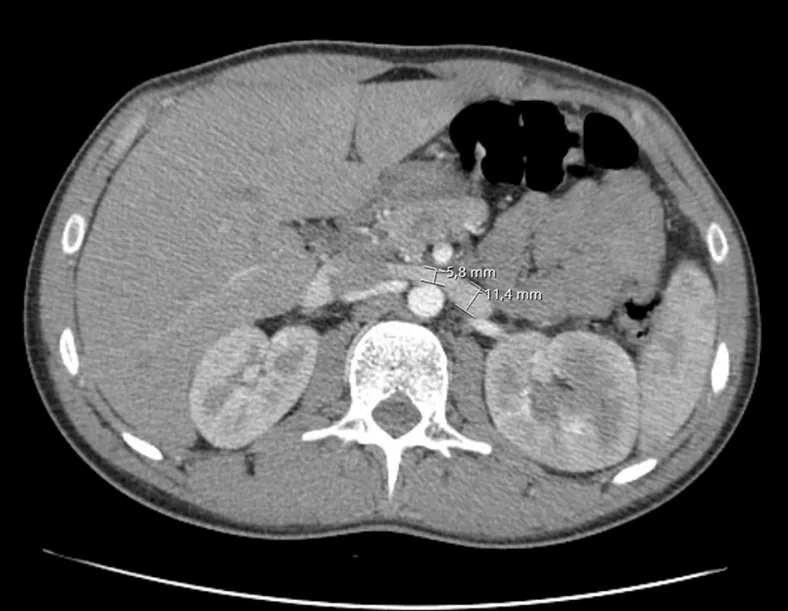

Dor lombar súbita e hipotensão em um paciente que o nefrologista é chamado para auxilar na investigação, quais pontos importantes do diagnóstico não podemos esquecer?

Valkercyo Feitosa

4 meses atrás